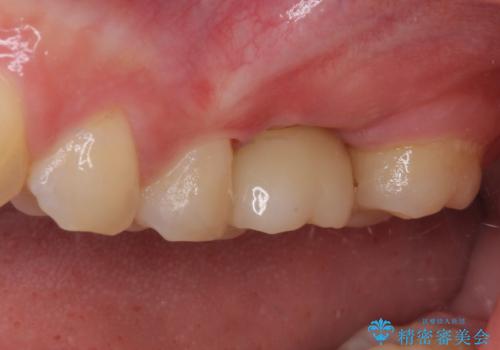

- 抜歯が必要と診断された奥歯を気にして来院された患者様です。

抜歯の上インプラントによる補綴治療を行うこととなりましたが、前歯の叢生も気になるとのことで並行して矯正治療を行うこととしました。

歯列不正は軽微であったので、インビザラインによる矯正治療とし、矯正治療中にインプラント埋入を行う予定としました。

痛みがないので、ボロボロのまま放置していましたが、抜歯後は汚れが溜まりにくくなりスッキリとしたようです。

前歯のデコボコも解消され、ブラッシングが楽になりました。